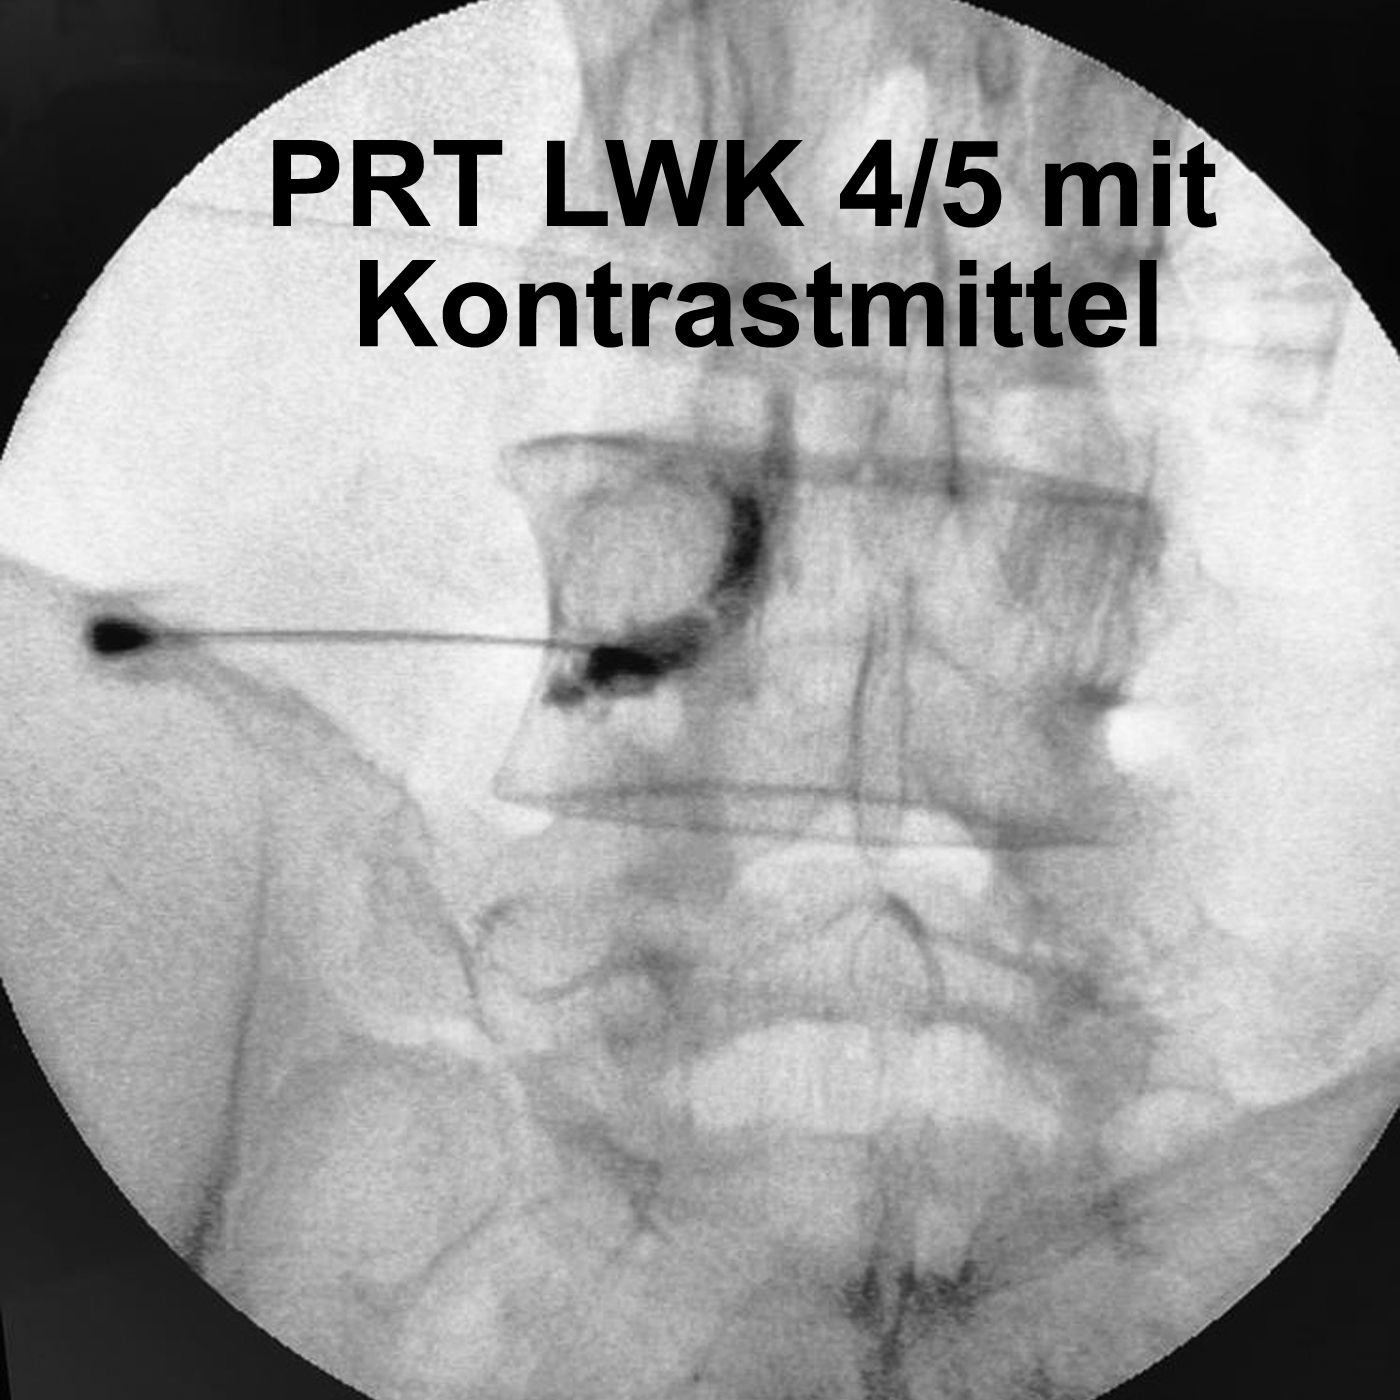

PRT: Der präzise Weg raus aus dem Ischiasschmerz

Stechender Ischiasschmerz, Brennen im Bein, jede Bewegung eine Qual – und dann die Frage: Muss jetzt wirklich operiert werden? Nicht unbedingt. In dieser Folge sprechen wir über die periradikuläre Therapie, kurz PRT – eine millimetergenaue Spritze direkt an die Nervenwurzel, die Schmerzen lindern und Operationen verhindern kann. Ich erkläre, wie die PRT durchgeführt wird und welche Bildgebung am besten funktioniert, um das Ziel zu erreichen.